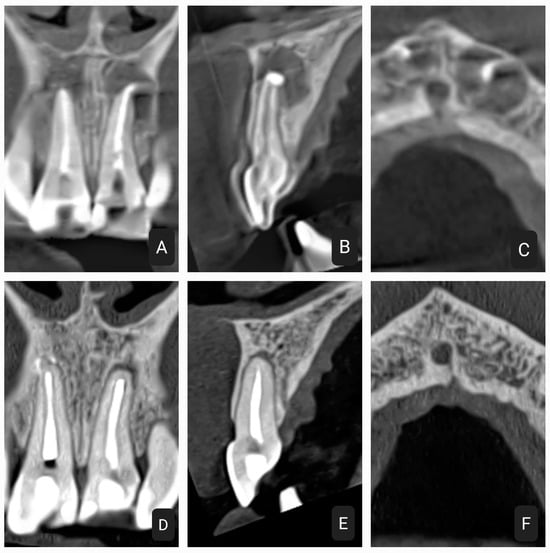

2.2. Second Case

2.3. Third Case

2.4. Fourth Case